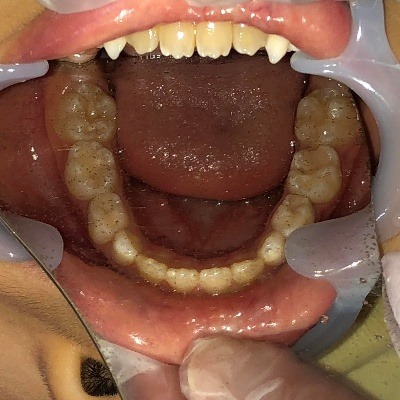

下顎

| 治療内容 | インビザライン・ファースト |

|---|---|

| 治療詳細 | 反対咬合や叢生、開咬を整えるために、歯の表面にアタッチメント(白い突起)をつけました。 また、顎間ゴムと呼ばれる引っ掛けるゴムの補助装置も用いて治療を行いました。 |

| 副作用 | マウスピースを1日約20時間装着する必要があるため、しっかりと装着いただけないと歯並びが綺麗になりません |